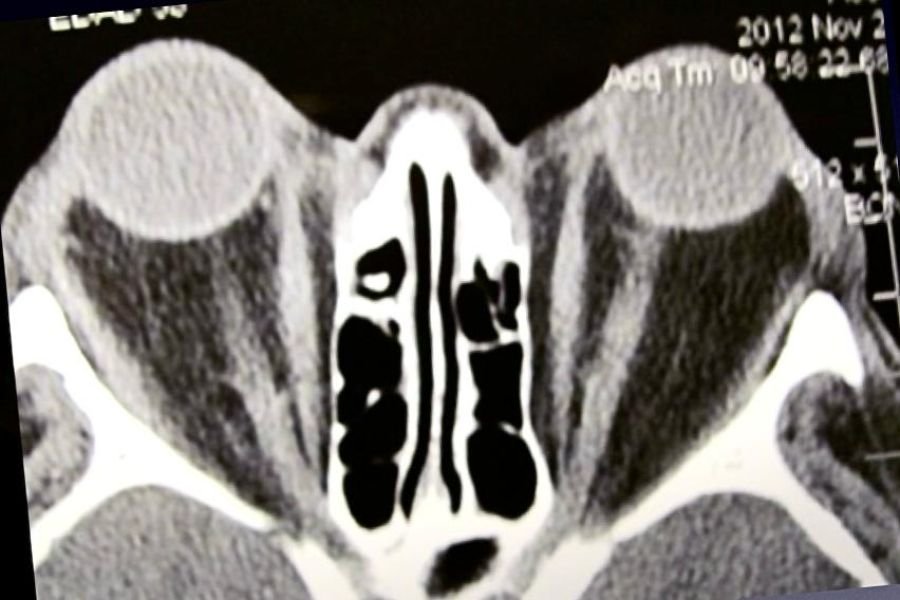

Curso Virtual de Ecografía Ocular 2025

Aprenda de expertos a interpretar imágenes ecográficas para un diagnóstico preciso de patologías oculares.

Con modalidad 100 % online asicrónica, acceso a material actualizado y flexibilidad horaria, es la oportunidad ideal para profundizar sus…